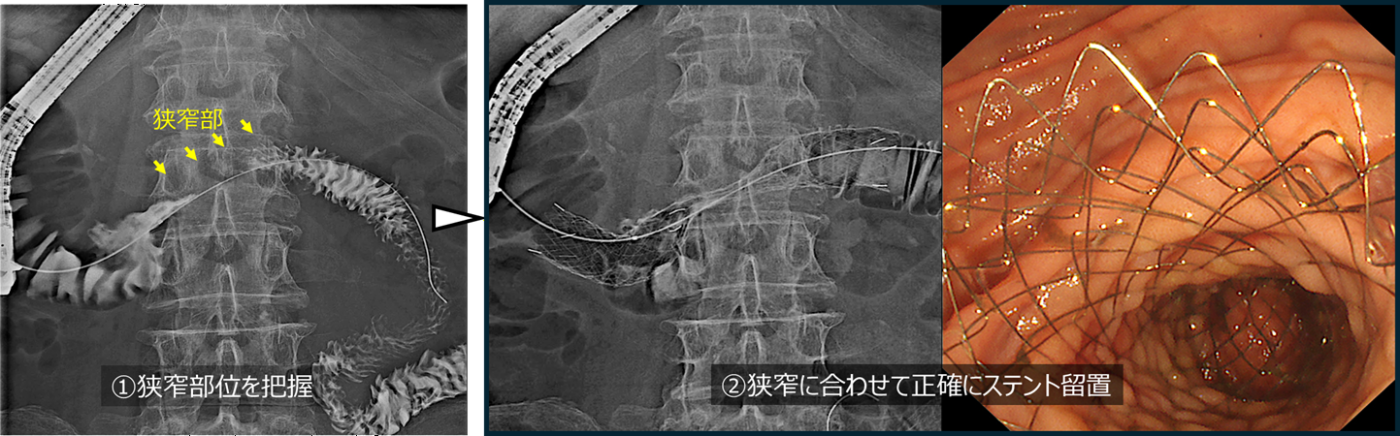

(6)十二指腸ステント留置

胆膵領域を含むさまざまな悪性腫瘍では、腫瘍が胃や十二指腸に浸潤することで消化管が狭くなり、食事が通らなくなることがあります。このような状態では、食事がとれなくなったり、嘔吐を繰り返したりすることがあります。このような消化管狭窄に対しては、外科手術によるバイパス術が行われることもありますが、内視鏡を用いて十二指腸にステントを留置することで、より低侵襲に消化管の通過を改善することが可能です。多くの場合、問題がなければ治療の翌日から食事を再開することができます。

膵頭部癌による閉塞性黄疸と十二指腸狭窄による嘔吐・食事摂取困難を主訴に受診されました。CTでは膵頭部癌の浸潤によって十二指腸の水平部が狭窄(黄色矢印)していました。内視鏡を挿入すると、同部位は高度に浸潤を受けており、嘔吐の原因と考えられました。

十二指腸造影を行い、狭窄部位を確認しました。続いて、狭窄部を十分にカバーするように十二指腸ステントを留置しました。ステント留置後、翌日より食事摂取可能となり、翌々日に退院しました。